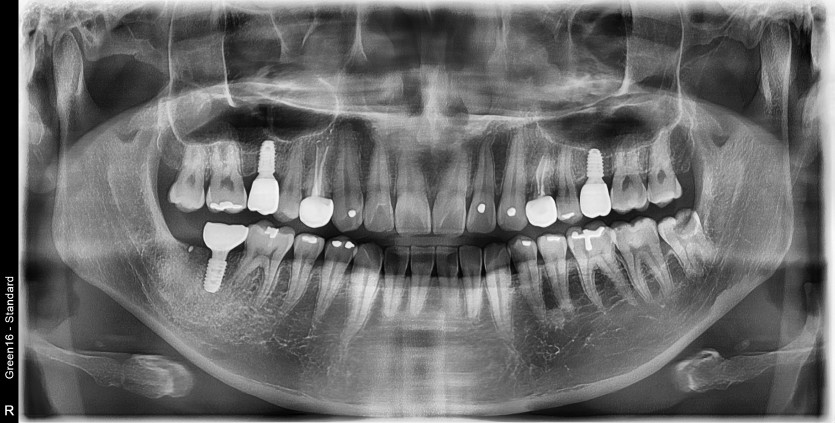

#28,38 사랑니 발치

구강 외과 전문의가 당일 발치했습니다.